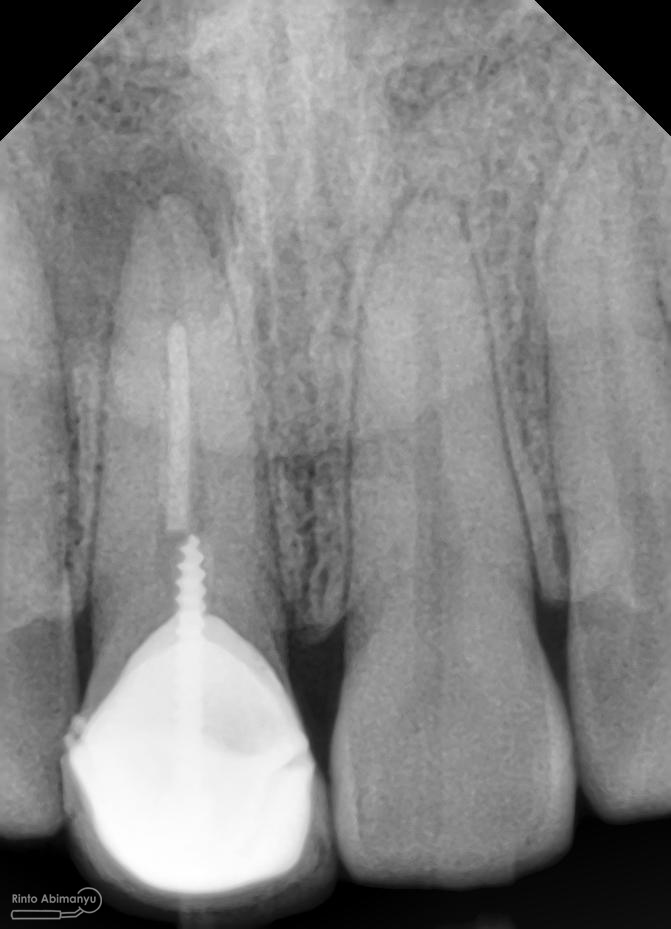

Oo iya tidak lupa juga dilakukan foto ronsen setelah pemasangan crown…

Foto radiografis akhir

Dari foto ronsen terlihat gambaran yang “indah” dari mulai pengisian saluran akar yang rapat dan padat serta gambaran sementasi mahkota yang terlihat homogen….